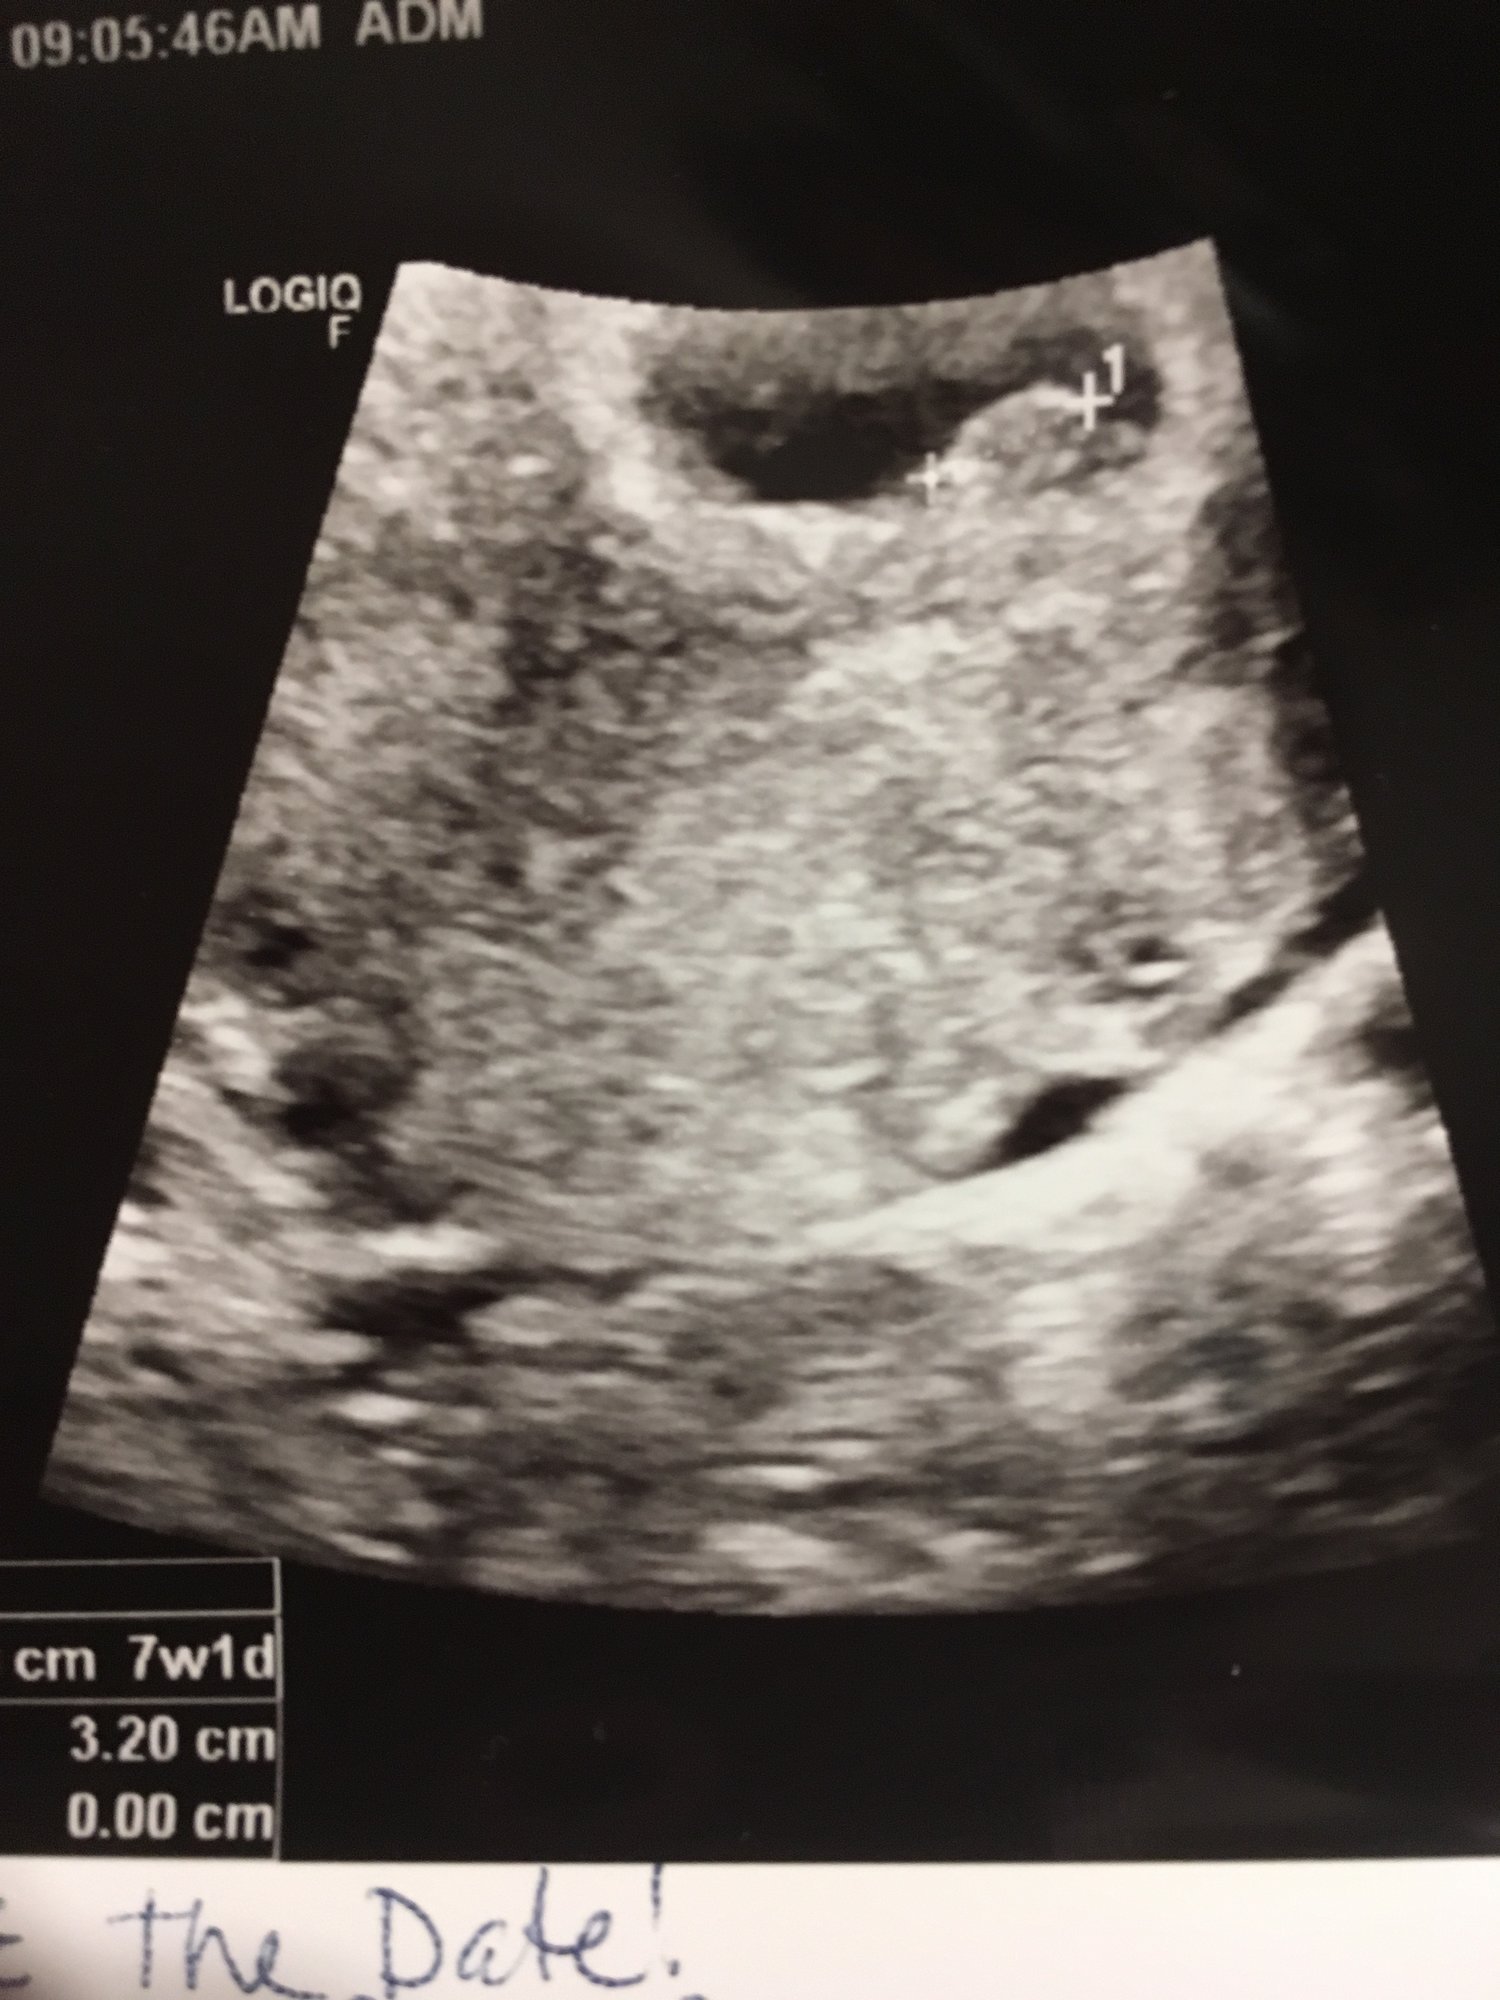

Here is our little bean, measuring 6+1 today. EDD is 3/28. Heart rate was in the mid-90's so we have a follow up ultrasound in two weeks!